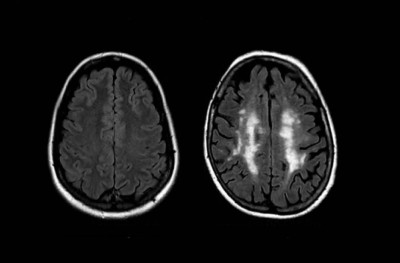

އުމުރުން ދުވަސްވުމުން ސިކުނޑިން މައުލޫމާތު ފޮނުވައިދޭ ބައި ކަމަށްވާ ވައިޓް މެޓާ އަކީ އުމުރުން ދުވަސްވާ ވަރަކަށް މަދުވަމުންދާ އެއްޗެކެވެ. ދިރާސާއިން ދައްކާފައި ވަނީ އެ މީހެއްގެ އުމުރާ އަޅާބަލާއިރު ސިކުނޑީގައި ވައިޓް މެޓާ ހުންނަންޖެހޭ ވަރު، އެ މީހަކީ އެކަށީގެންވާ ވަރަށް ވުރެ ބަރު މީހެއް ނަމަ މާބޮޑަށް މަދުވާ ކަމަށެވެ. މާނަ އަކީ އުމުރުން 50 އަހަރުގެ މީހަކު އޭނާގެ އުމުރާ ނުބައްދަލު ބަރުދަނެއްގައި ހުންނަ ނަމަ ސިކުނޑި 60 އަހަރުގެ މީހެއްގެ ސިކުނޑިއާ އެއް ހާލަތެއްގައި ހުރުމެވެ.

ޖުމުލަ ގޮތެއްގައި ބަލާއިރު، ބަރު މީހުންގެ ސިކުނޑީގައި ވައިޓް މެޓާ މަދެވެ. އެކަމަކު މި ތަފާތު ސިކުނޑިން ފެންނަން ފަށަނީ މެދު އުމުރަށް އެޅުމަށް ފަހުގައި ކަމަށް ވެސް ދިރާސާގައި ބުނެފައިވެ އެވެ.